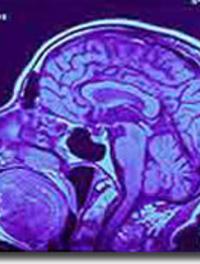

Le virus Zika (ZIKV) est un pathogène réémergent découvert en Ouganda, en 1947 chez le macaque, puis chez l’homme en 1954. Depuis 2007, plusieurs épidémies à ZIKV ont permis de mettre en évidence une fœtopathie sévère, plus grave que celle liée au cytomégalovirus (CMV) à la toxoplasmose et à la rubéole. Elle est associée à une infection maternelle du premier semestre de la grossesse et entraîne des conséquences cliniques catastrophiques, voire une mort in utero. La gravité [...]